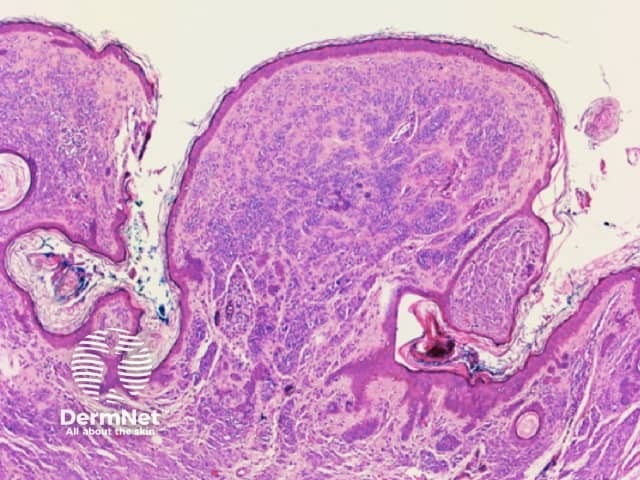

Seborrhoeic keratoses are amongst the most variable lesions on dermatoscopy, which is reflected in their protean histological appearances (Figure 15). Aside from the pseudopod pattern, any pattern or colour can be found. Flat seborrhoeic keratoses appear similar to solar lentigo on dermatoscopy. With early epidermal acanthosis thin curved lines (Figure 13) and circles become manifest, whilst with advanced acanthosis thick curved lines (Figure 14) and clods typically predominate. White clods are due to keratin under the stratum corneum. Orthokeratotic loosely laminated surface keratin appears yellow. Crypts fill with discoloured keratin and may appear various colours on dermatoscopy including brown and orange (Figure 15).

Figure 13 Figure 14 Figure 15

Figure 15a Figure 15b Figure 15c